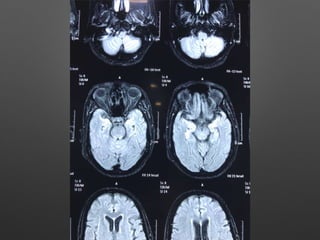

HOPI • Patient wasapparently normal till 5pm 3/2/18, started behaving abnormally like half dressed, with carrying comb and want to go temple, with irrelevant talks. • Relatives observed paucity of left Upper and lower limb, thinking of stroke - took her to near by hospital • Asked for imaging - after imaging she developed 2 episodes of left sided jerky movements of both UL & LL with twitching over the face - lasted for 1-2 min, treated with sedative , Inj. insulin for high CBG - 495 mg/dl and referred here for further management.

Provisional Diagnosis • ?Acuteischemic stroke - left hemiparesis with focal seizures • ? Hyperglycemic encephalopathy • ? Viral encephalitis

Investigations • HB- 14.1gm%- 12.2 • WBC- 15990cells/cumm - 10770, -P 83%, L-9%,M-7% • Platelets - 3.3lakhs - 2.8 • ESR- 63mm/hr • RBS - 267 mg/dl • CUE - N • RFT - N • LFT - N • S.Na - 137, k+ - 3.9, Mg- 2.1, Ca- 9.1, Ph- 3.5, Ammonia- 0.29

• ECG -N • 2DEcho- N • U/S - Abd- Gr I Fatty liver changes